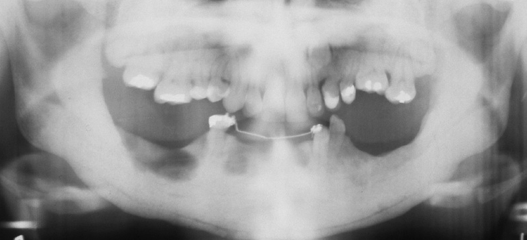

cherubism